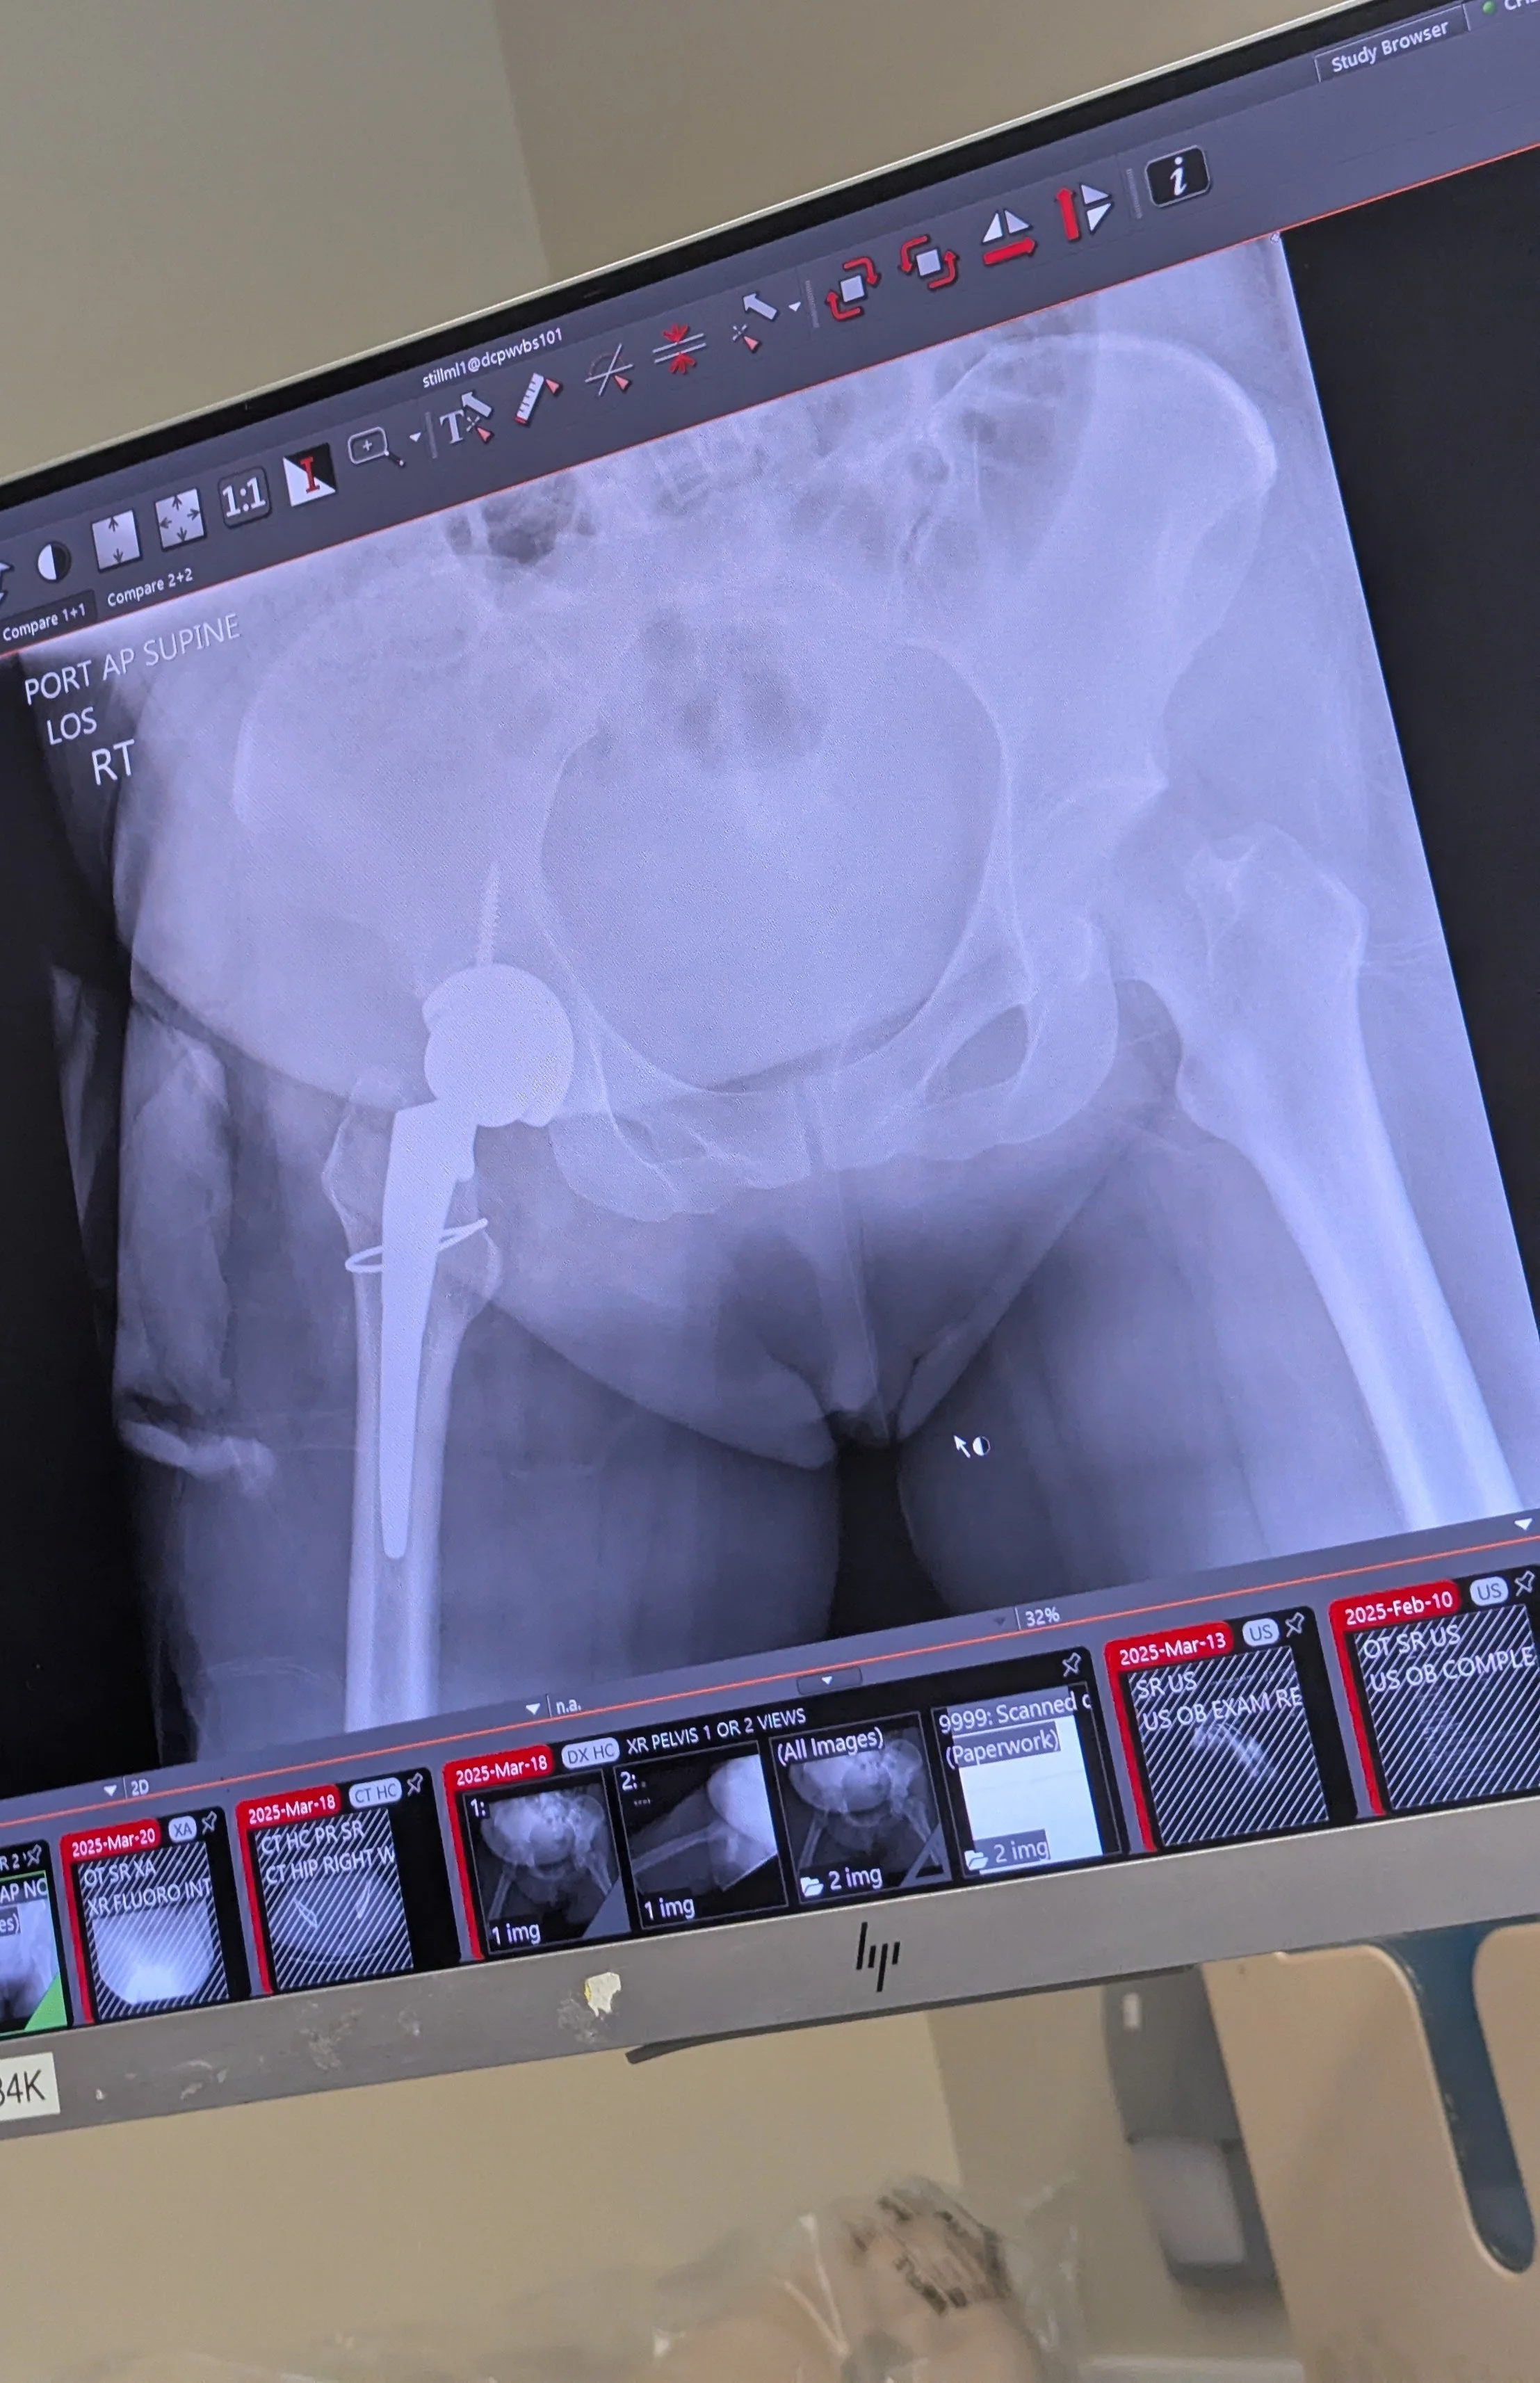

My new hip!

The doctors told me I needed to get hip replacement surgery so, two days later, I was transported to another campus (Sutter CPMC Mission Bernal Campus & Orthopedic Institute) where an orthopedic surgeon could perform the operation. At this point, I had only seen our twins once after delivering because the NICU was only accessible by foot or by wheelchair and I was stuck in bed due to my hip. I have to give a special shout-out here to the NICU doctor, Terri Slagle, and the team of nurses Meghan, Michelle, and Mary who knew I hadn't had the chance to see or hold my babies since delivering. They measured my hospital bed to make sure it would fit in the NICU room and through the doors, and wheeled me down to hold my babies before I had to go to the other hospital campus. I was upset about needing to get another surgery, and being able to hold my babies when I knew I wouldn't be able to see them for who knows how long made me so happy that I cried right then and there!

We didn't get a chance to talk to Dr. Peter Callender until right before the surgery when a consent form needed to be signed, but we were told that a hip replacement was the only option due to the nature of the break. Cue another spinal tap and surgery (this time I was completely unconscious), but that surgery also went well and now I have a metal ball in my hip that will be the bane of my existence whenever I need to fly. And, in another turn of events, I was told post-surgery that I needed to get a bone density scan because Dr. Callender noticed that my bone was abnormally soft during the operation, and he had to reinforce the hip replacement 🫠 But once again, the surgery went smoothly and Dr. Callender and his team made sure I was taken care of physically and emotionally before and after!